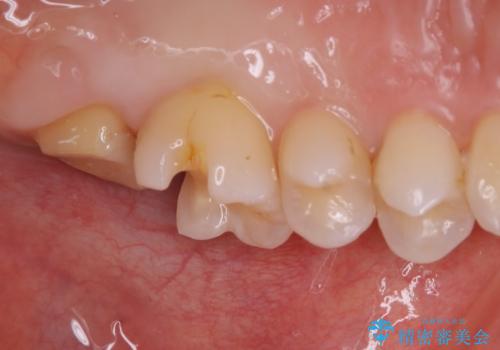

根管治療をした歯は神経のある歯と比較して強度が下がり、長期的に破折のリスクが高まると言われています。破折のリスクを軽減させるため、根管治療を行った歯に対しては歯冠をすべて覆うクラウンという被せ物にて補綴処置を行います。

セラミックは強い咬合力がかかると割れてしまうリスクがあります。今回のケースでは、歯を削る量をなるべく少なくしたいとの患者様の強い希望により、セラミックインレーを作製しました。破折してしまった場合には、歯牙全体を覆うクラウンにすることを十分説明し、ご理解いただいたうえで装着しております。